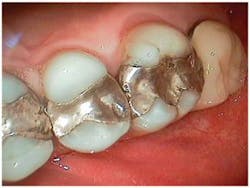

Full arch, occlusal images, as part of a photographic series, are an important adjunct to the new-patient examination. Images of only one or two teeth, such as those commonly captured with an intraoral camera, center on single-tooth dentistry but do little to help clinicians, staff, or patients think about patient needs in a comprehensive fashion (Fig. 1). The way clinicians evaluate and communicate with patients should be in alignment with the way they wish to treat their patients. Patients can better understand their needs when they can clearly see the "big picture." Full arch, occlusal images are an excellent way to help patients see the big picture and should be part of any new-patient examination (Figs. 2 and 3).